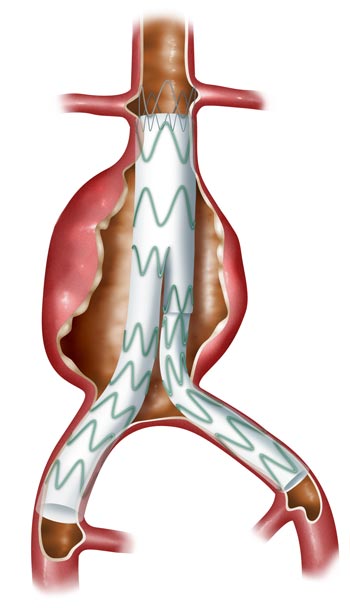

Endovascular Repair

A less invasive option is endovascular repair (EVAR). Instead of opening the abdomen, I make small cuts in the groin and thread a fabric-and-metal tube (a stent graft) up through the blood vessels, using x-ray guidance, to line the aneurysm from the inside. Recovery is quicker – usually only 2 to 3 days in hospital. The trade-offs are that EVAR needs lifelong follow-up scans, and not everyone's anatomy is suitable, so open repair is sometimes the better choice.

Endovascular Repair

Endovascular

Procedures

Less invasive percutaneous procedures to repair blood flow through the aorta to intestines, organs and extremities.

Endovascular abdominal aorta aneurysm repair